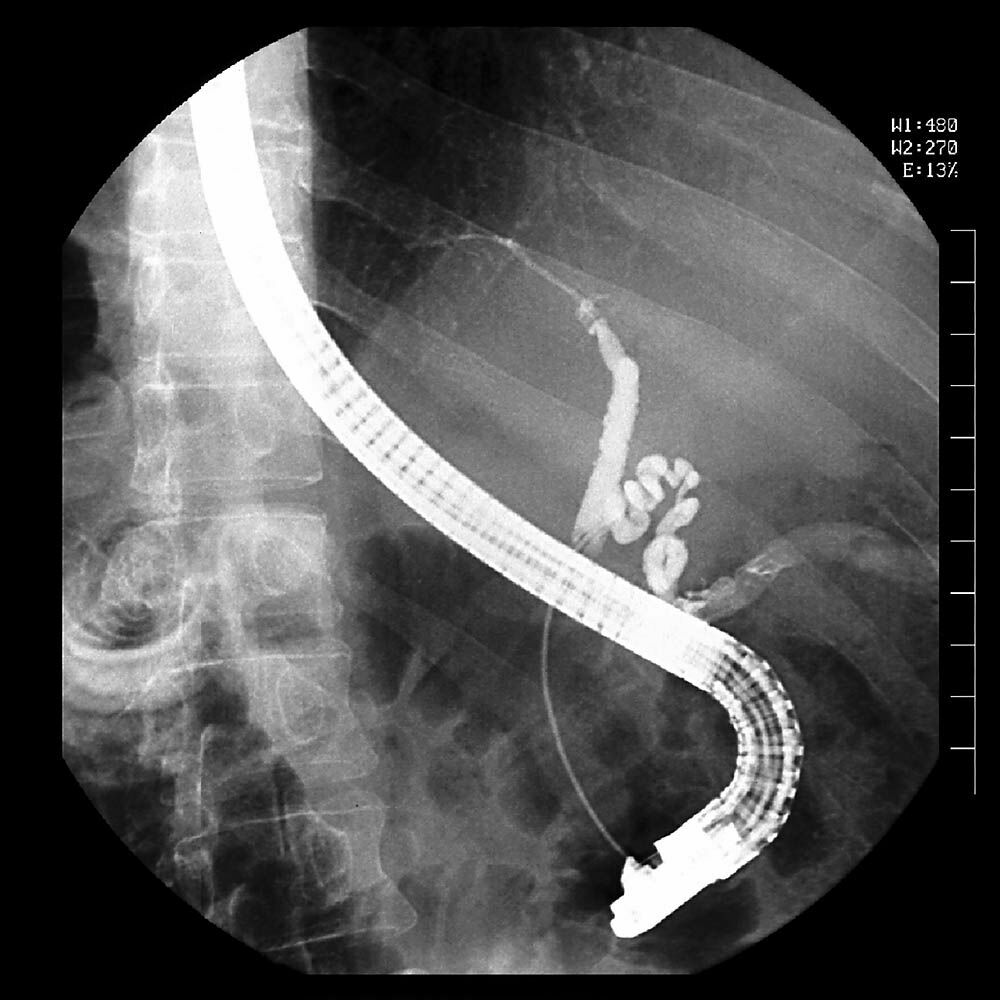

ERCP (Endoskopik Retrograd Kolanjiyo Pankreatografi), safra kanallarındaki taşların tedavisinde hangi avantajları sunuyor? Uzm. Dr. Adil Duman, bu yöntemin safra kanalları ve pankreatik kanalın incelenmesinde radyolojik tekniklerle birlikte özel bir endoskopi yöntemi olduğunu açıkladı. Safra kanalındaki taşların çıkarılmasında sıkça tercih edilen bu yöntem, hastaların şikâyetlerini hızlı bir şekilde gidermekte.

ERCP, cerrahi müdahalenin yerine neden tercih ediliyor? Uzm. Dr. Adil Duman, ERCP'nin başarı oranının yüksek olması ve komplikasyon riskinin az olması sebebiyle tercih edildiğini ifade etti. Ayrıca, safra kanalı ve pankreas kanserleri veya safra kesesi ameliyatları sonrası kaçak durumlarında da kullanılan bu yöntem, cerrahiye göre daha az risk içeriyor.

ERCP işlemi nasıl gerçekleşiyor ve ne gibi sonuçlar doğuruyor? Uzm. Dr. Adil Duman, ERCP'nin genellikle hastanın uyutularak yapıldığını ve işlemin ortalama 15-20 dakika sürdüğünü belirtti. İşlem sonrasında hastaların genellikle aynı gün taburcu edildiğini ve hızlı bir iyileşme süreci yaşadıklarını dile getirdi.